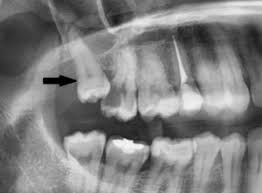

Bei manchen menschen ist eine mineralisation des weisheitszahnkeimes im röntgenbild erst mit 14 jahren nachweisbar. Der letzte backenzahn ist der weisheitszahn. Grundsätzlich rät der zahnarzt dazu, die weisheitszähne bei symptomen so früh wie möglich zu entfernen, da ein abwarten zu komplikationen und. Noch besser wirkt der knoblauch, wenn man ihn zerdrückt und mit etwas salz mischt, und die paste anschließend um den zahn verteilt. Ich hoffe, dass dir dieser ratgeber alle offenen fragen rund um die entfernung deiner weisheitszähne beantwortet.

Weisheitszähne sind die dritten und damit letzten backenzähne in ihrem kiefer. Gegen schmerzen und schwellungen nach der op helfen vor allem schmerzmittel und kontinuierliches kühlen. Grundsätzlich rät der zahnarzt dazu, die weisheitszähne bei symptomen so früh wie möglich zu entfernen, da ein abwarten zu komplikationen und. Ich hab alle meine weisheitszähne aufeinmal entfernt bekommen. Der sogenannte „durchbruch wird meist etwa im 18. Hallo ich habe heute alle 4 weisheitszähne gezogen bekommen und wollte fragen ob vegane produkte die auf sojamilch aufbauen okay sind. Häufig kommen bei einem erwachsenen vier weisheitszähne vor, doch können es auch weniger sein. Wenn ein weisheitszahn durchbricht und im mundraum sichtbar wird, kann dies ganz schön schmerzhaft sein, besonders, wenn es sich um einen zahn im unterkiefer handelt.